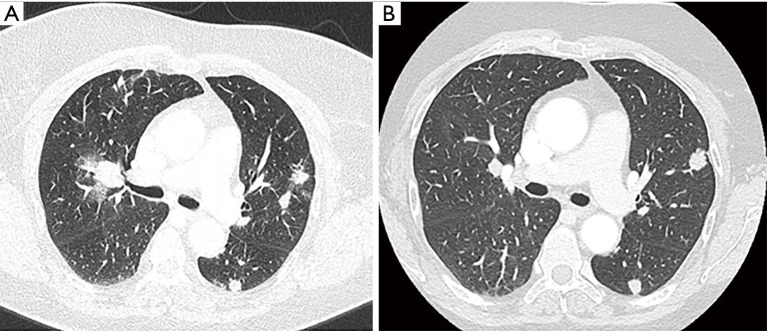

Case description: A 75-year-old woman with EC (MSI-H) with pulmonary and bone metastasis progressed on first line chemotherapy platinum-containing, was treated with dostarlimab as monotherapy. Medical history was positive for arterial hypertension, autoimmune thrombocytopenia and allergy to amoxicillin and levofloxacin. After the second administration of dostarlimab, our patient showed a dramatic improvement of her clinical conditions. The clinical response was confirmed by radiological response on the basis of the results of a computed tomography (CT) scan performed in March 2023 that showed a reduction of the pelvic mass and pulmonary secondaries. No toxicities related to autoimmune thrombocytopenia occurred. The experienced grade 2 infusion reaction, resolved with the suspension of the drug and the administration of an antihistaminic drug; then we resumed dostarlimab doubling the administration time.